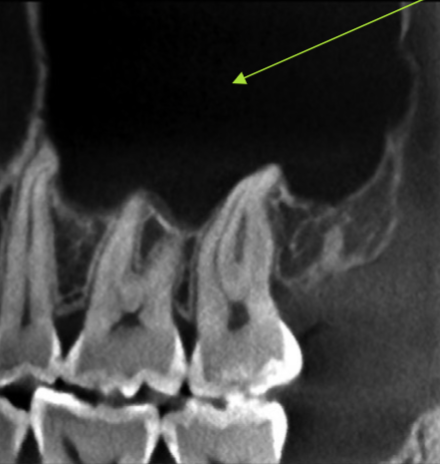

maxillary sinus

what is indicated by the GREEN dot

ostium (of maxillary sinus)

identify the structure

apical of roots

at what level is this